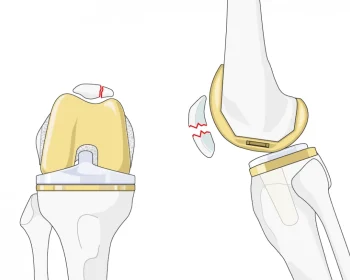

Patellar resurfacing is a procedure that smooths and resurfaces the underside of the kneecap, reducing pain and improving movement in cases of cartilage damage.

Surgery for recurrent patellar dislocation involves stabilizing the kneecap through realignment and soft tissue repair, enhancing joint stability and preventing future dislocations.